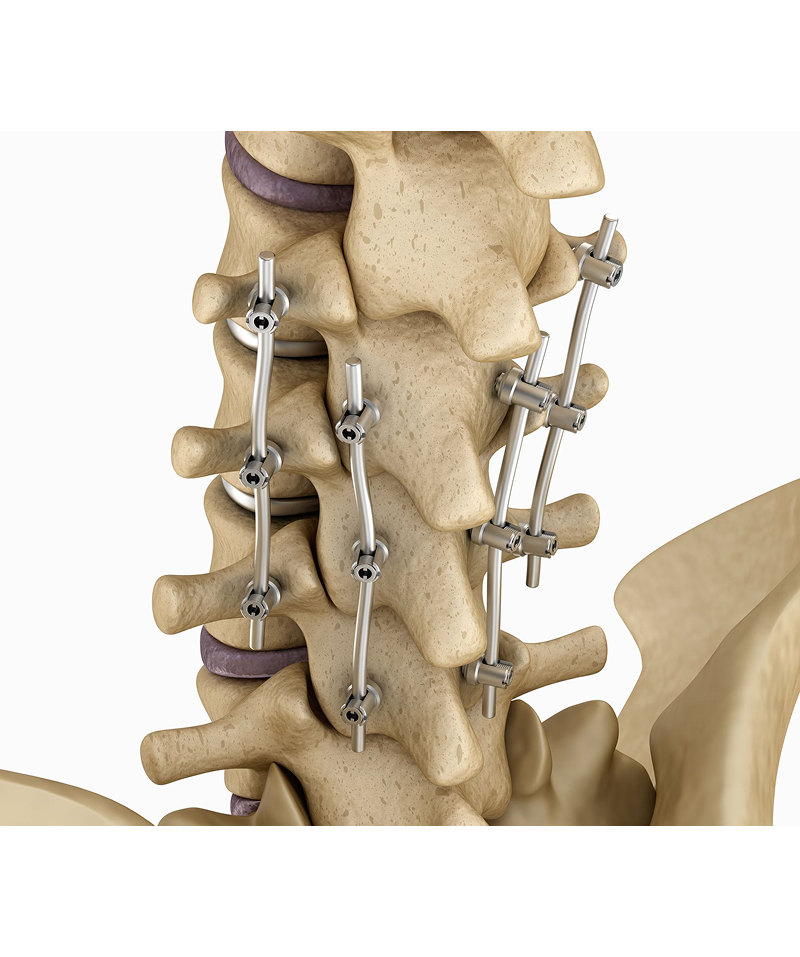

Spinal Fusion

Fuses two or more vertebrae to stabilize the spine. Spinal fusion surgery involves joining two or more vertebrae (spinal bones) together to prevent movement between them, aiming to relieve pain and stabilize the spine. This procedure is often performed when other treatments, like physical therapy or medication, haven't been successful.

Purpose: Spinal fusion aims to stop painful movement between vertebrae, which can occur due to conditions like arthritis, spinal stenosis, or injuries.

Procedure: During surgery, a surgeon may remove the disc between the vertebrae and place bone grafts (from the patient's own body, a donor, or artificial materials) to stimulate bone growth and fusion.

Types of Fusion: There are various types of spinal fusion, including anterior, posterior, and transforaminal lumbar interbody fusion (TLIF), each with different approaches to accessing the spine.

Benefits: Spinal fusion can significantly reduce pain, improve spinal stability, and correct spinal deformities.

Risks and Recovery: Like any surgery, spinal fusion carries risks such as infection, nerve damage, and non-union (failure of bones to fuse). Recovery time varies, but it generally takes several weeks to months, with full recovery potentially taking up to six months.